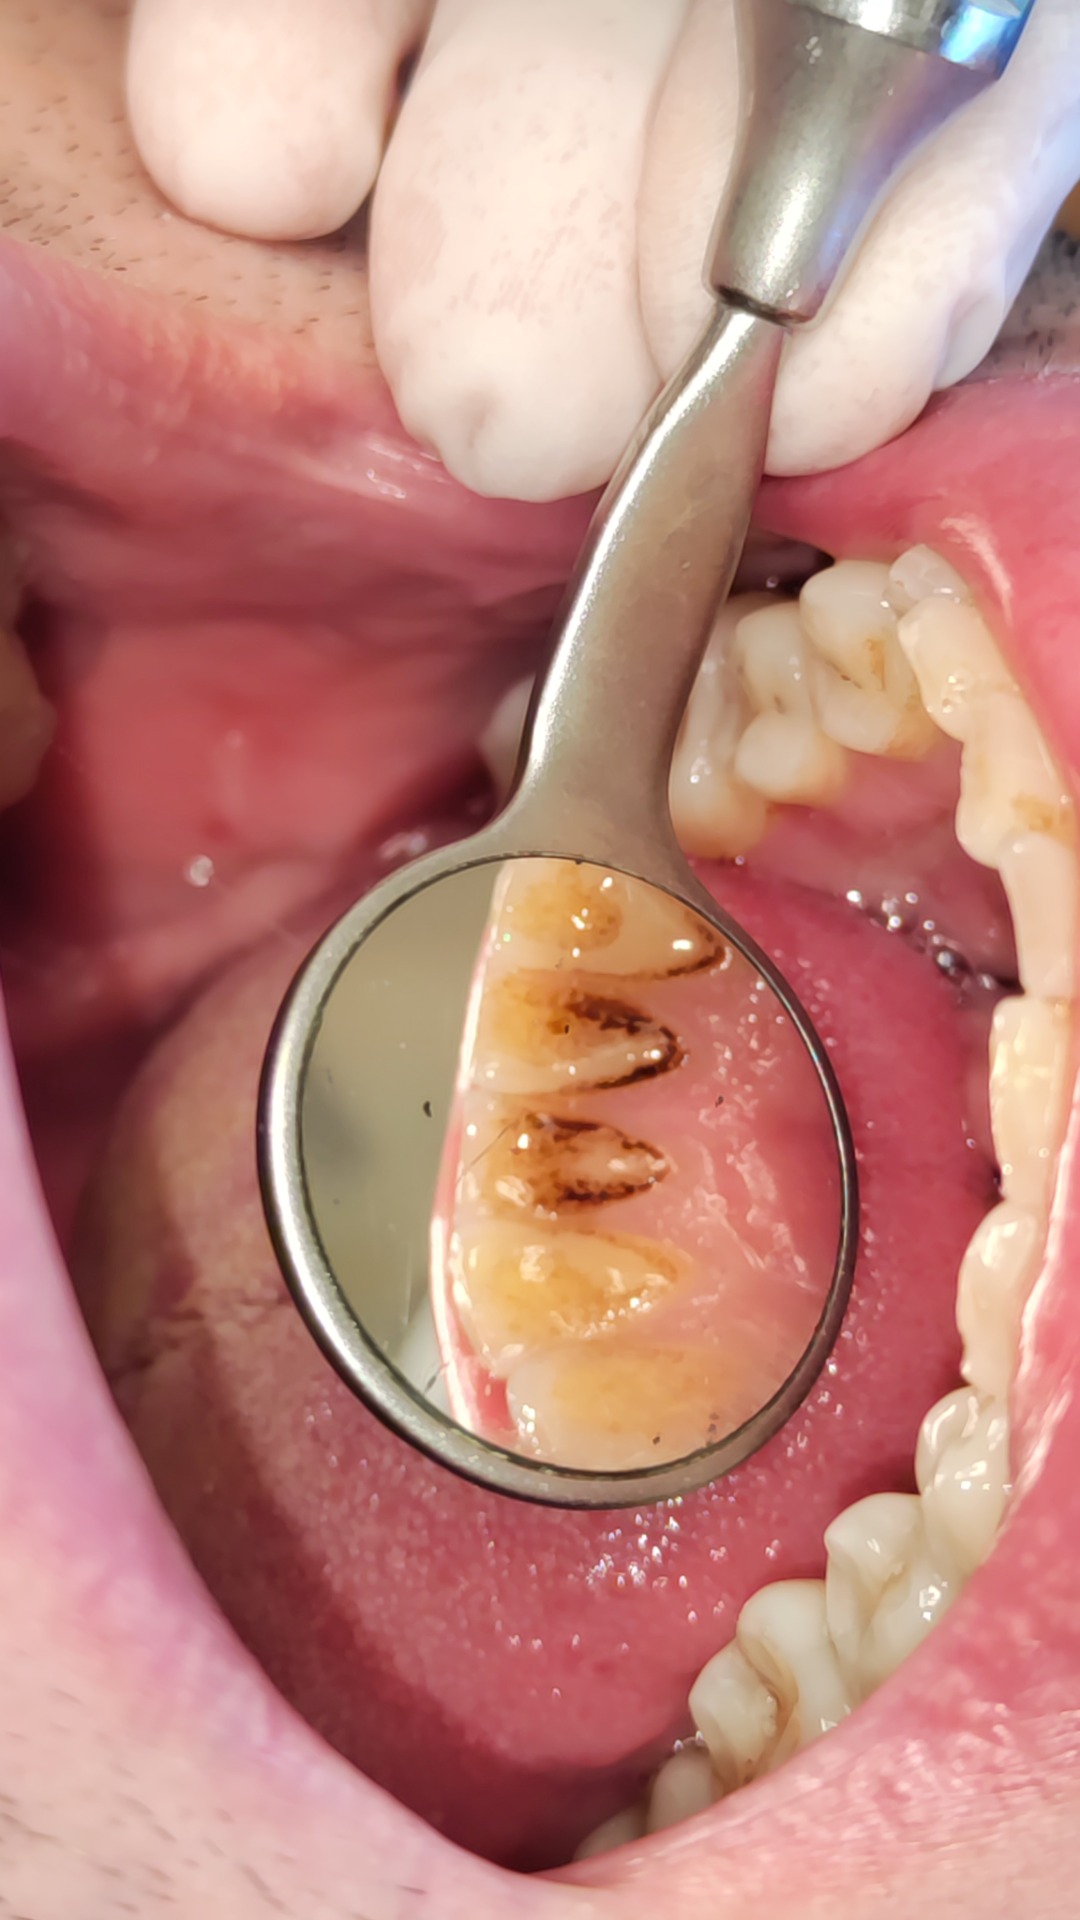

Pravidelným čištěním odstraňujete doma lepkavý film na povrchu zubu – plak. Neodstraněný plak např. v těžko dostupných nebo při nedostatečné péči však časem mineralizuje a tvoří se tvrdý zubní kámen. Plak a zubní kámen obsahují bakterie, jejichž produkty způsobují zánět dásně. Ten se pak projevuje krvácením, zápachem z úst apod. Dlouhodobý zánět už ohrožuje závěsný aparát zubu a může vést ke ztrátě zubů. Bakterie v místě zánětu jsou pak podkladem i pro vznik zubního kazu.

- scaling aneb profesionální čištění povrchu zubů. Jedná se o odstranění plaku a zubního kamene z povrchu zubů nad a pod dásní pomocí ultrazvuku a speciálních ručních nástrojů.

- deep scaling a root planing je metoda hloubkového očištění a vyhlazení povrchu kořene zubů v případě přítomnosti parodontálních kapes.

Intervaly návštěv jsou stanoveny individuálně po vstupním vyšetření. Při nevyhovující hygieně tzn. velkém nánosu zubního kamene postupujeme step-by-step. Na vstupní návštěvě očistíme zuby "z nejhoršího" nad dásní a po zlepšení domácí péče a ústupu zánětu dočistíme i pod dásní. Při velkém zánětu dásně více krvácí a hlubšímu ošetření tak brání nepřehledný terén i vyšší citlivost při ošetření.